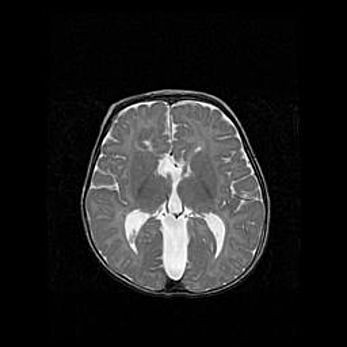

Церебральная ишемия II.

Возраст: 5 дней

Вес: 3400 г

Пол: женский

Окружность головы: 35 см

Срок гестации: 39 недель

Церебральная ишемия – это заболевание, характеризующееся недостаточностью (гипоксией) либо полным прекращением (аноксией) снабжения мозга кислородом по причине закупорки одного или нескольких сосудов. Это приводит к  что метаболическим расстройствам различной степени тяжести в тканях головного мозга, развитию коагуляционных некрозов и гибели нейронов.